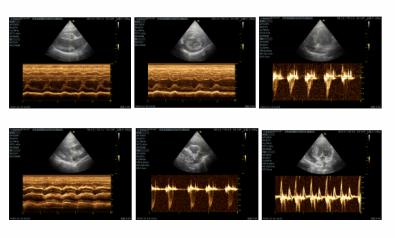

超声检查↓↓

心脏超声提示:二尖瓣瓣膜增厚,左心室壁增厚、欠光滑。